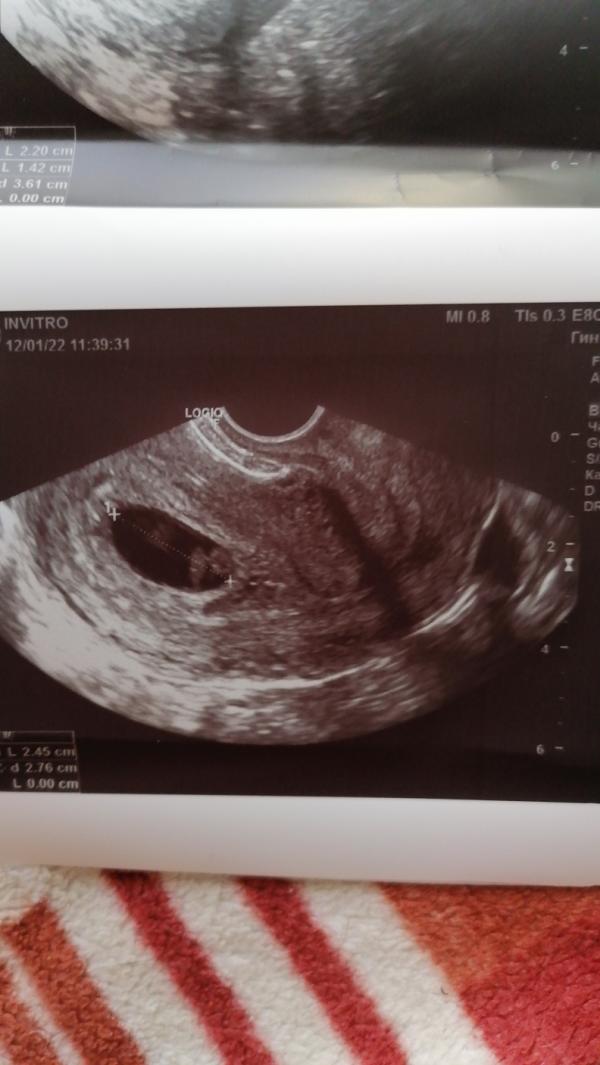

Наше первое узи. Поставили срок 6 недель и 6 дней.